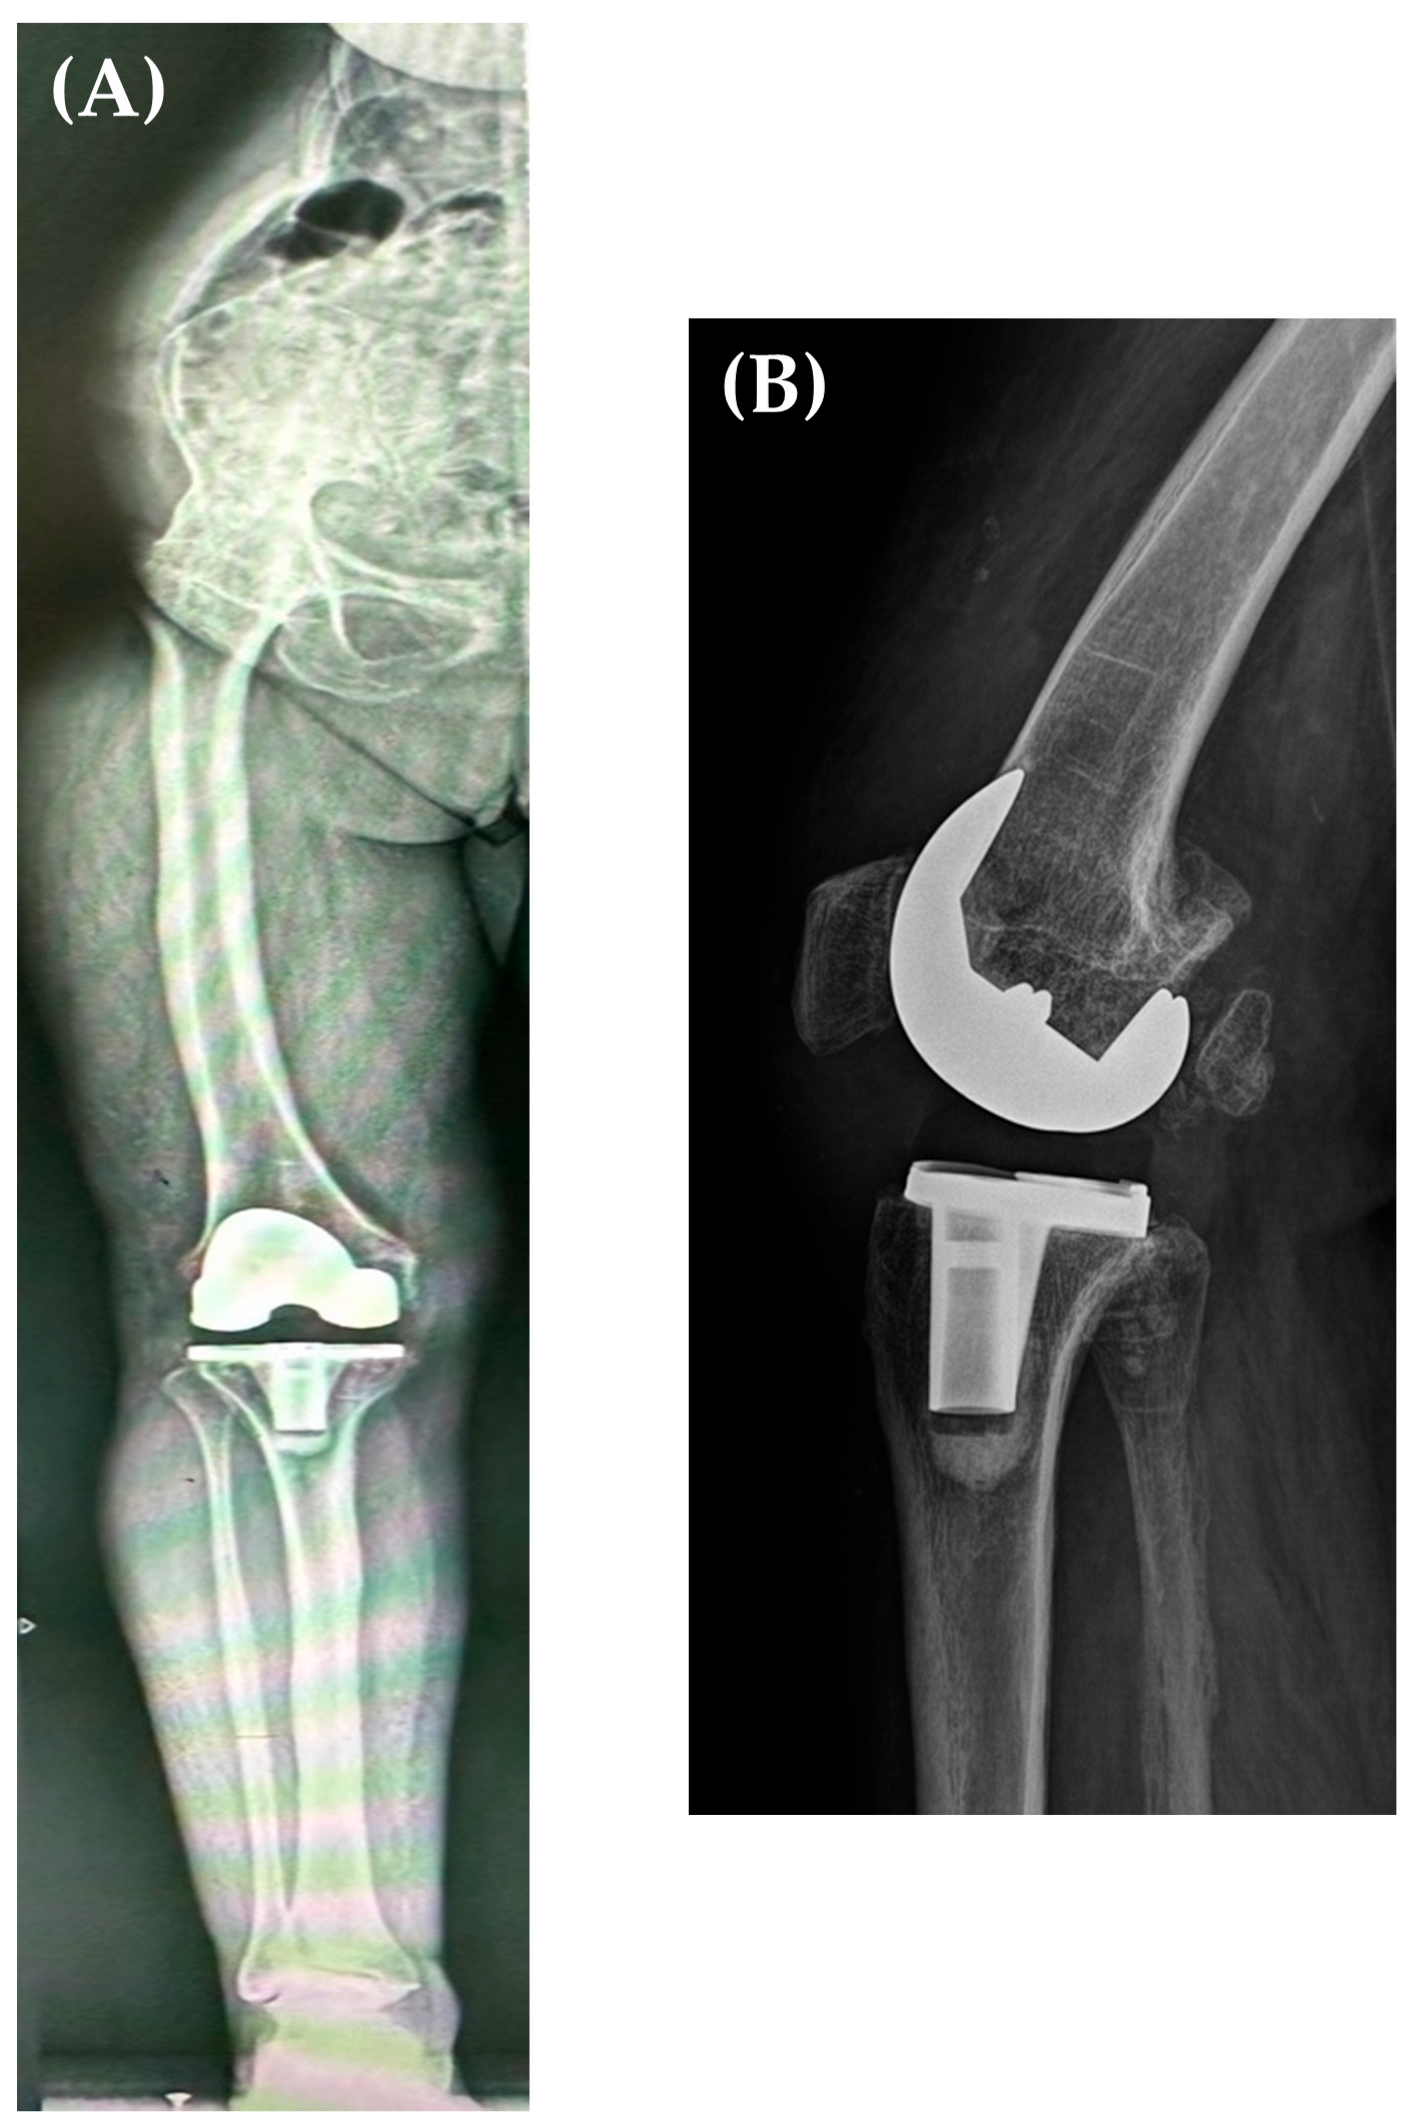

A total knee replacement was performed using a cemented postero-stabilized (PS) prosthesis (NexGen) through a medial parapatellar approach, using the extension gap first technique [15]. This type of implant was chosen due to the fact that the patient had competent collateral ligaments, and the ideal flexion-extension gap was intraoperatively obtained using a PS insert. Having the knee flexed and the foot stable on the operating table provided optimal conditions for this surgery. Knee extension was held by a surgical assistant when needed; bone cuts were made according to the preoperative plan (Figure 5A,B).

Postoperative X-rays revealed adequate positioning and sizing of the prosthetic components and a restored alignment of the lower limb. Personalized rehabilitation was initiated 24 h after the surgery, with knee flexion being recovered at the edge of the bed, and knee extension in lateral decubitus; weight bearing was allowed on the 1st postoperative day, and the patient started walking with the aid of crutches. Subsequent periodic radiological follow-ups at 3, 6, 12 months and annually up to 5 years (Figure 6A,B) did not show any signs of loosening (Figure 3). At her 3-month follow-up, the patient had an active range of motion (ROM) of 110° knee flexion and full extension (in lateral decubitus), walking without any aiding devices, with an increase in KSS from 26 to 84 points and WOMAC increase from 40 to 77.

Figure 6. Five years postoperative AP long leg X-ray (A) and sagittal X-ray (performed at 30° of knee flexion) (B) showing the correct alignment of the femoral and tibial prosthetic components, neutral alignment of the right lower limb, and no component loosening.